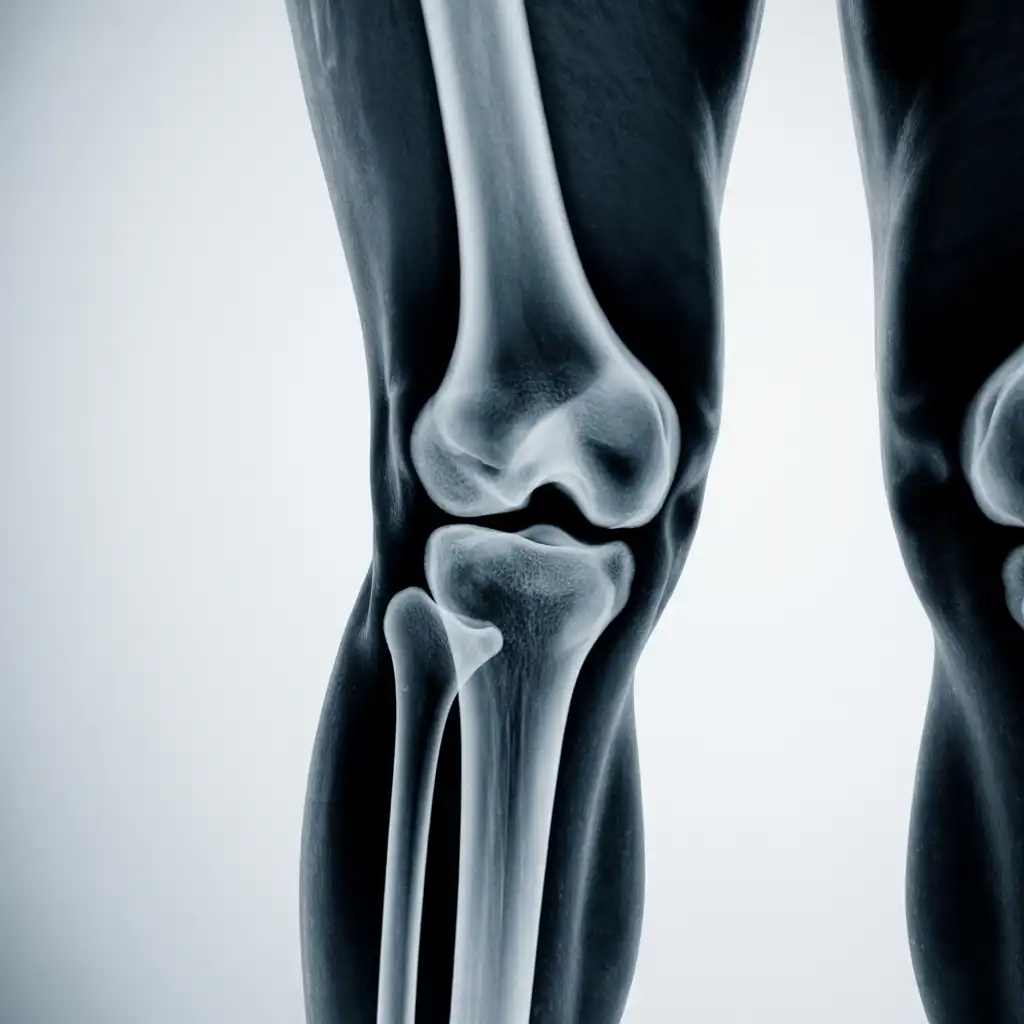

Il professionista entra con apparecchiature a basso dosaggio e schermi protettivi: bastano 2 × 2 m di spazio vicino al letto o alla poltrona. In pochi minuti acquisisce immagini HD, proprio come in un reparto ospedaliero.

Le immagini (formato DICOM) vengono caricate su un server crittografato e inviate immediatamente al radiologo. Se servono scatti aggiuntivi, il tecnico resta in collegamento video per eseguirli al volo.

Il medico radiologo analizza le immagini e firma il referto digitale all’istante. Ricevi il referto cartaceo e le immagini su chiavetta USB consegnati direttamente a casa tua subito dopo l'esame.

Usiamo le stesse apparecchiature certificate CE dei reparti ospedalieri, calibrate regolarmente. I referti sono validi per visite specialistiche, pronto soccorso e pratiche assicurative, e restano archiviati per 10 anni per ogni esigenza futura.